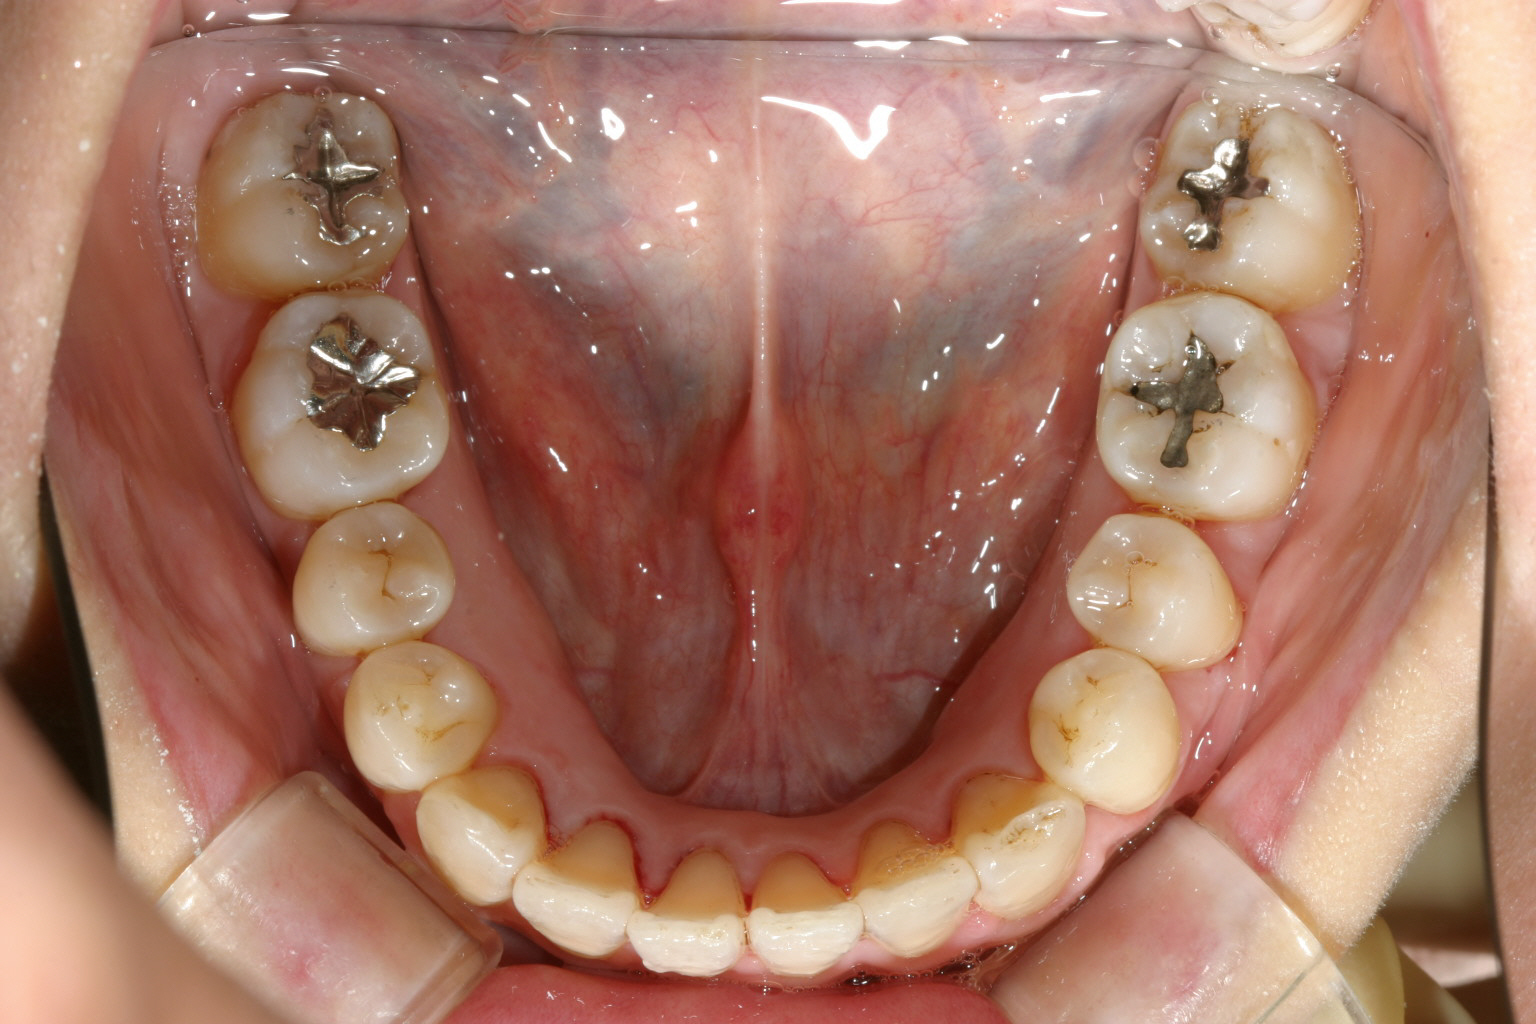

1年2か月後です。 マルチループが入っています。アーチの形状は殆ど改善致しました。

下顎もマルチループの外側に太いマリガンワイヤーが入っています、この太いワイヤーのお陰で内方に倒れていた臼歯が立ってきました。

綺麗に改善しました。

下顎も申し分有りません。